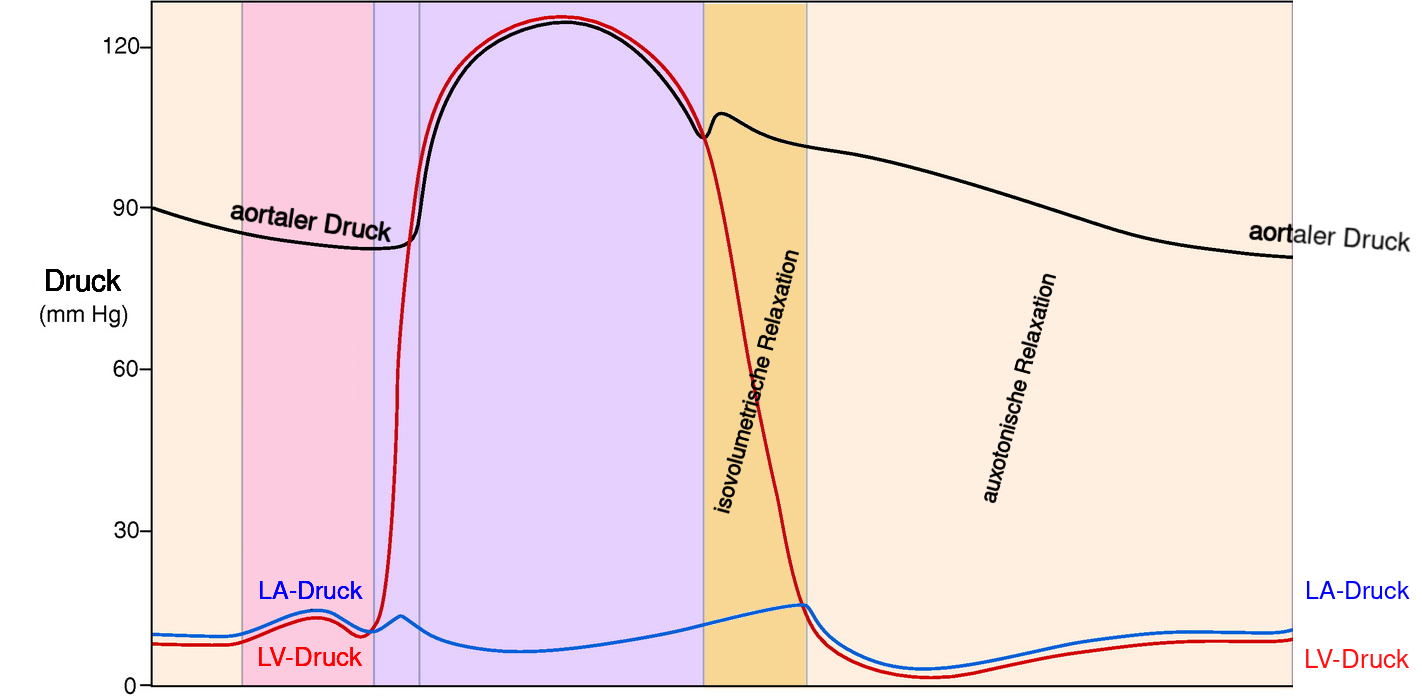

2 Phasen Herzaktion

- der ventrikulären Systole ist die atriale Systole vorgelagert

Vorhofkontraktion (atriale Systole)

- aktive linksventrikulären Füllung

- trägt zu 20 bis 30 Prozent zum gesamten linksventrikulären Füllungsvolumen bei

- erhöht normalerweise den diastolischen Druck hierdurch um weniger als 5 mmHg

die ventrikuläre Systole (kardialer Output)

- durch die Kontraktion hervorgerufene Inwärtsbewegung der Herzmuskelwand steigt der Druck in der Herzkammer —

- wenn der Druck in den Herzkammern den Druck in der Aorta übersteigt, wird Blut ausgeworfen —

die ventrikuläre Diastole (kardialer Input)

- entscheidend für die linksventrikuläre Füllung und damit der Herzfunktion

- für die Füllung muss der LV-Druck kleiner als der LA-Druck sein

- diastolischer LV-Druck wird bestimmt durch intraventrikuläres Blutvolumen, ventrikuläre Dehnbarkeit (Compliance) und durch den von Herzbeutel und rechter Herzkammer auf den linken Ventrikel ausgeübten externen Druck

1. Phase Diastole: isovolumetrische Relaxation

- Zeitraum zwischen Aortenklappenschluss und der Mitralklappenöffnung

- Druck im linken Herzen nimmt bei gleichbleibendem Volumen ab

- rascher Druckabfall

- Aufdrehen (Untwist) und elastische Rückfederung (Recoil) des linken Ventrikels ➙ Saugeffekt ➙ Mitralklappenöffnung und Ventrikelfüllung führt

2. Phase Diastole: auxotonische Relaxation

- Zeitraum zwischen Mitralklappenöffnung und atrialer Kontraktion

- mit Mitralklappenöffnung füllt linker Ventrikel mit variablen Druck

- in späterer Phase Entspannung sämtlicher Herzmuskelzellen

- linke Ventrikel nun nachgiebig, leicht dehnbar und weist normalerweise nur minimalem Widerstand gegenüber Füllung auf